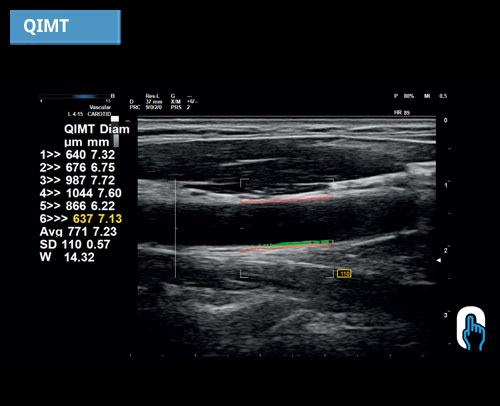

QIMT: Automatická detekce tloušťky média Intima v reálném čase na základě analýzy RF signálu.